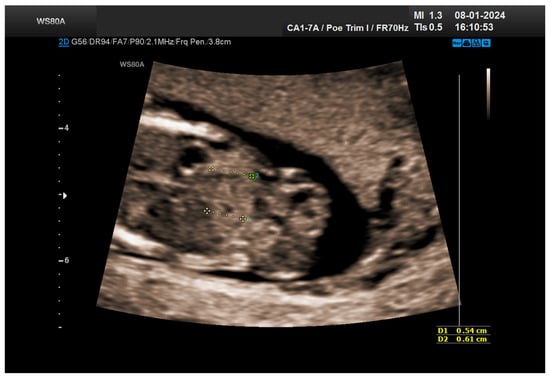

The combined test result indicated a low risk for trisomies, preeclampsia, and intrauterine growth restriction. However, during the ultrasound examination, the absence of the right renal tissue in the right parasagittal sections was noted (Figure 1). Examination of the embryo in axial sections demonstrated the presence of a relatively well-defined acoustically heterogeneous echogenic mass situated anterior to the spine, in sonographic contact with the renal tissue image correctly occupying the left lumbar fossa (Figure 2). Those aspects suggested the existence of a renal anomaly of crossed fused renal ectopia. No other embryonic anomalies were detected, the bladder image was present, and the amniotic fluid volume was normal. The calculated gestational age corresponded to the ultrasound estimate. The suspicion of crossed fused renal ectopia was maintained during a subsequent reevaluation at 17 weeks of pregnancy (Figure 3 and Figure 4).

Figure 2. Crossed fused kidneys at 13 weeks.